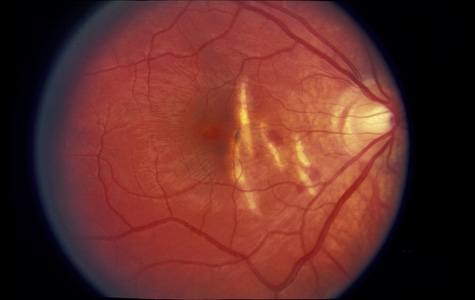

Commotio retinae (Latin, meaning retinal contusion) is a contrecoup injury. It can occur peripherally (Fig. 8) or centrally, in which case it is called Berlin's edema (Fig. 9). Immediately and for several hours after the trauma, the retina appears normal, although the patient may complain of decreased vision. Thereafter, the outer layers of affected retina become opaque. On fluorescein angiography, the opaque retina blocks background choroidal fluorescence, and in most cases there is no leakage into or under the retina (Fig. 10). For years, clinicians had difficulty explaining this blockage, because leakage is expected in conditions with edema. It was then shown in experimental animals and in human autopsy eyes that Berlin's edema is not true edema. The retinal opaqueness is the result of intracellular edema and fragmentation of the photoreceptor outer segments and intracellular edema of the underlying pigment epithelium. There is little or no intercellular fluid.66–69

Fig. 8. Peripheral commotio retinae. The retinal blood vessels are clearly seen because the retinal whitening is in the outer retinal layers.

Fig. 9. Commotio retinae in the macula (Berlin's edema). The visual acuity was 20/25 at the time of the photograph and later improved to 20/15.

The visual acuity in commotio retinae varies from 20/20 to 20/400 and does not always correlate with the degree of retinal opacification. There is no known treatment. The prognosis is usually excellent except in cases with associated subfoveolar choroidal rupture and in cases with choroidal rupture with subfoveolar hemorrhage. Poor visual recovery can also be expected in cases with severe retinal pigment epithelial damage. Serous retinal detachment (Fig. 11) signals this condition, which can be confirmed by leakage of fluorescein into the subretinal space.70